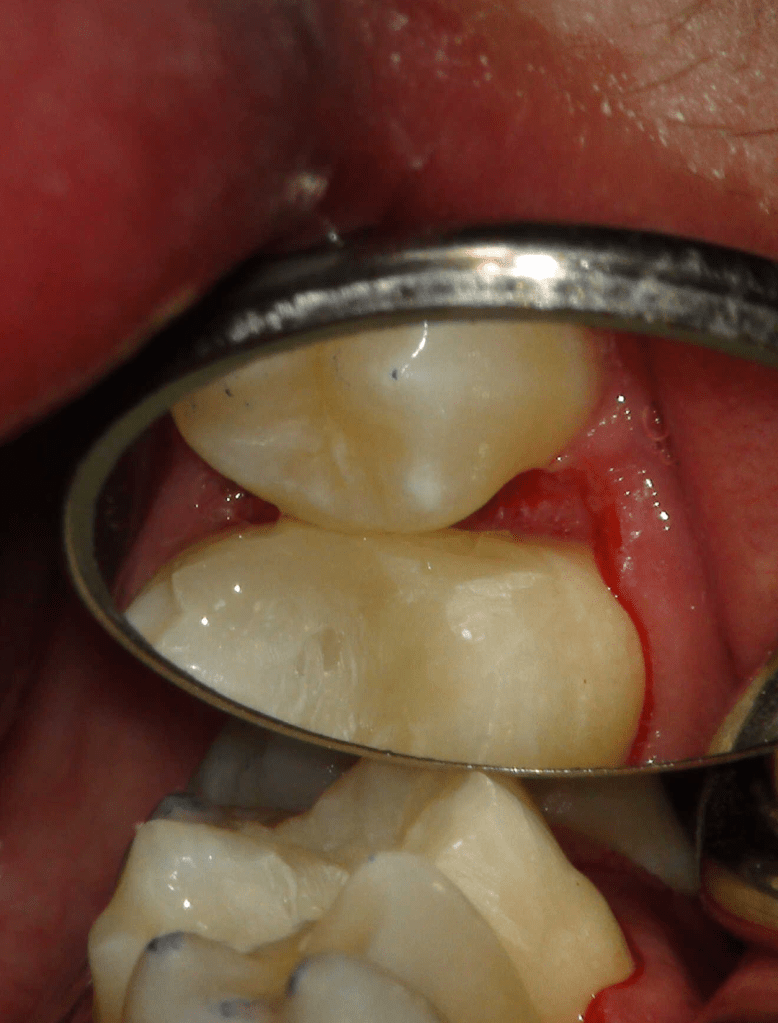

Pulpotomía biodentine + reco preendio